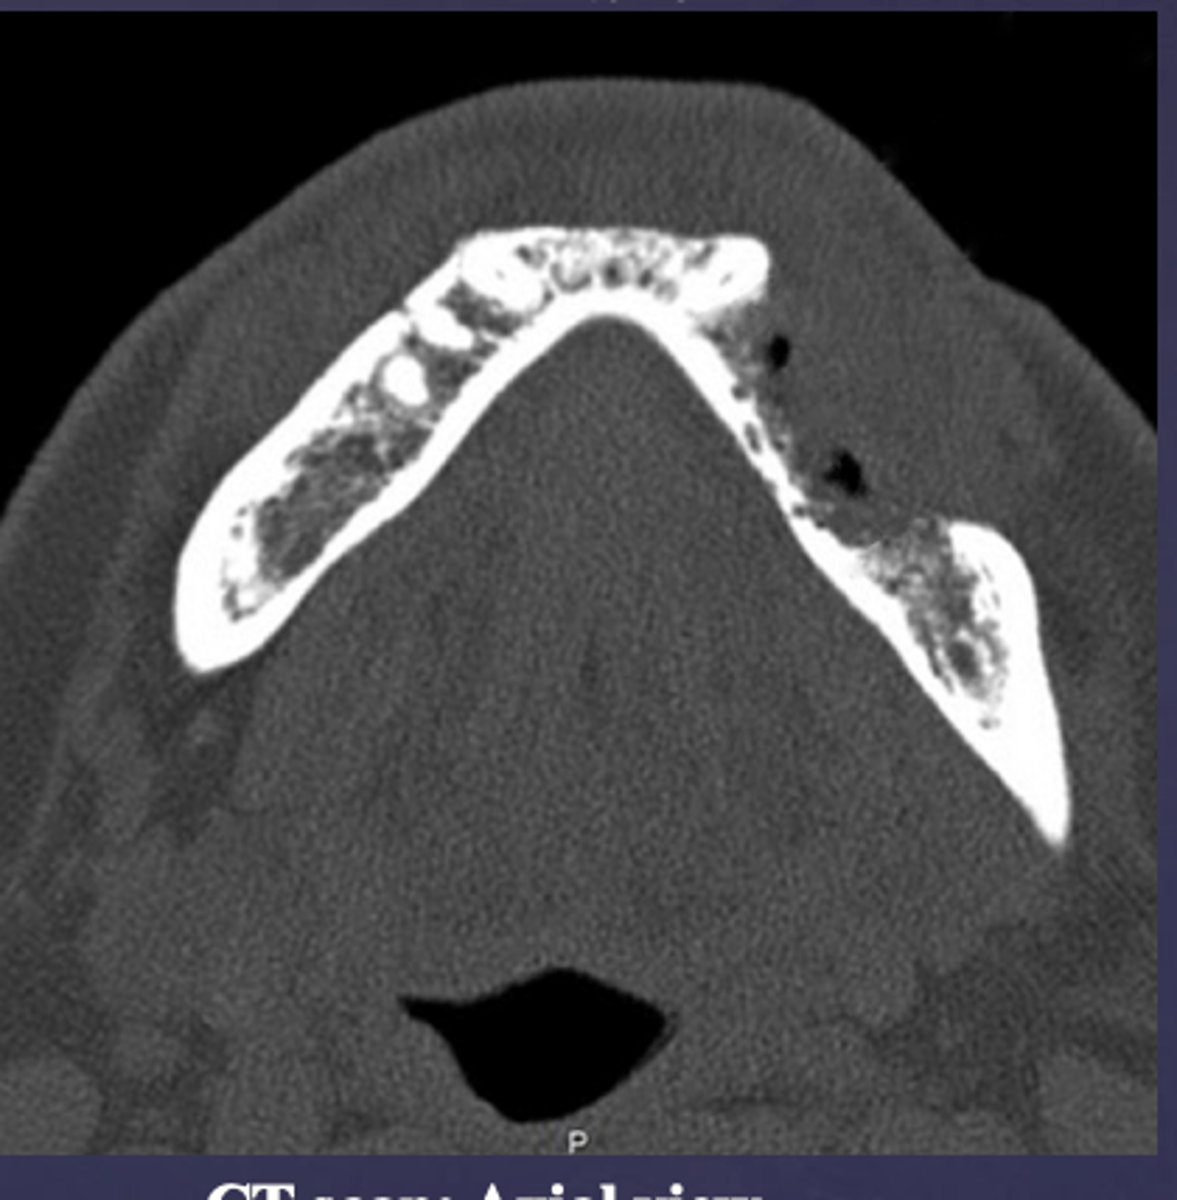

What is happening here?

periosteal reaction

Proliferative periostitis is also known as what?

onion skin

What occured?

Destruction of buccal cortex (ill defined radiolucent area in the mandible)

Osteomyelitis caused what to occur?

Pathologic fracture